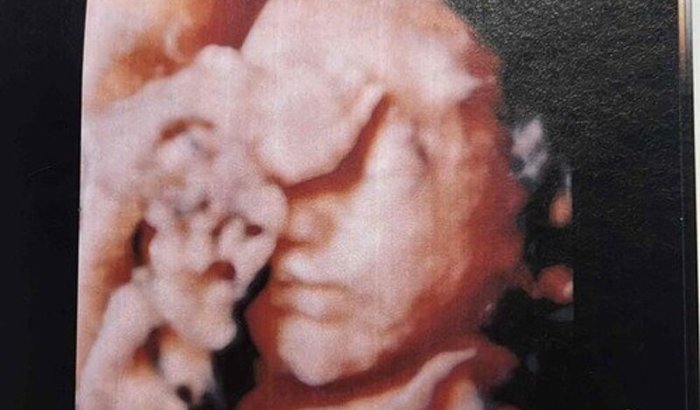

Com 22 semanas de gestação, no ultrassom morfológico, foi descoberto uma alteração no coração da Ana Liz, fomos até uma médica cardio pediatra e realizamos o ecocardiograma 3 vezes, onde ela foi diagnosticada com Síndrome da hipoplasia do coração esquerdo, que é uma malformação cardíaca rara e grave, que se caracteriza pelo subdesenvolvimento das estruturas do lado esquerdo do coração.